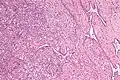

Micrografia do rete testis envolvida por seminoma. Mancha de H&E.

Micrografia do rete testis envolvida por seminoma. Mancha de H&E. -